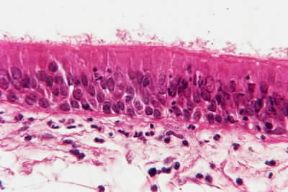

sf. [sec. XIX; da mucoso]. Membrana di rivestimento della superficie interna di organi cavi e di canali dell'organismo comunicanti con l'esterno direttamente o indirettamente quali, per esempio, le vie respiratorie, il tubo gastrointestinale, le vie urinarie, l'apparato genitale, l'orecchio medio, ecc. In corrispondenza delle aperture naturali verso l'esterno (bocca, narici, vagina, orificio uretrale, ecc.) la mucosa si continua con la epidermide, mediante una porzione di transizione caratterizzata da una struttura intermedia fra mucosa e cute "I disegni schematici della mucosa di alcuni organi è a pag. 251 del 15° volume. " . La mucosa è formata da un tessuto delicato, elastico, dal colorito grigio-roseo, mantenuto sempre umido dal secreto di ghiandole contenute nel suo spessore o direttamente prodotto dall'epitelio ghiandolare che la costituisce. Pur con certe differenze proprie dei singoli apparati, le mucose sono essenzialmente costituite da un epitelio che tappezza la cavità dell'organo o il lume del canale e, più profondamente, da uno strato di tessuto connettivale fibrillare (tonaca propria o derma della mucosa), che ha funzioni di sostegno e può essere ricco di fibre elastiche e di linfociti. La superficie di contatto tra epitelio e connettivo può a volte esser piana, a volte invece accidentata per la presenza di papille nella tonaca che penetrano nell'epitelio stesso. "Per i disegni schematici della mucosa di alcuni organi vedi il lemma del 13° volume."